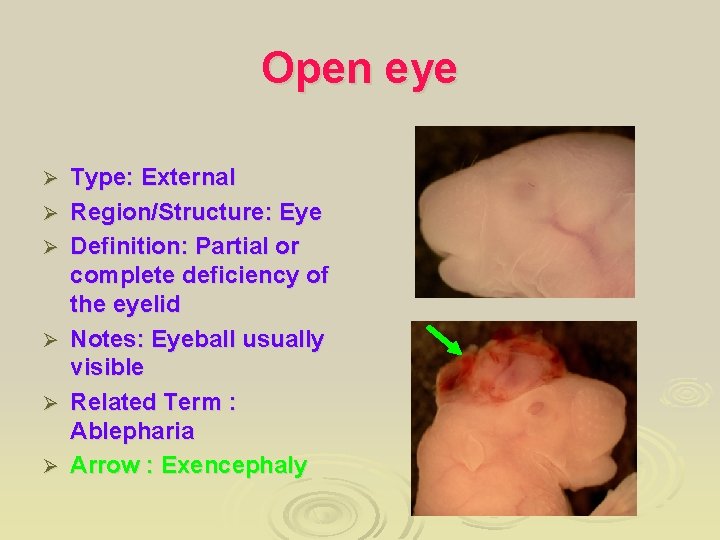

Open eye Ø Ø Ø Type: External Region/Structure: Eye Definition: Partial or complete deficiency of the eyelid Notes: Eyeball usually visible Related Term : Ablepharia Arrow : Exencephaly